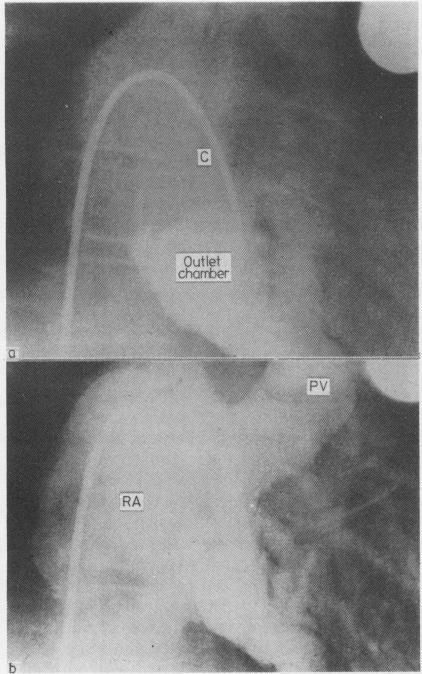

Fontan's correction has been performed without early death in 24 consecutive patients with tricuspid atresia. Eighteen patients had ventriculoarterial concordance (group I) and six discordance (group II). Late death related to infections occurred in three patients. The follow-up time in group I (16 survivors) ranges from 1 year 10 months to 7 years 5 months (mean 3 years 8 months) and in group II (five survivors) from 2 years 1 month to 5 years 6 months (mean 3 years 6 months). Early postoperative cardiac catheterisation showed arterial pulsatile pressure recordings in the pulmonary artery only in two patients in group I, in whom a valved conduit was used to connect the right atrial appendage with the outlet chamber. Patients with a valved conduit connected with either the pulmonary artery (group II) or the outlet chamber (two patients of group I) showed better preservation of right atrial contractions angiocardiographically and scored better in exercise tests than did patients with a non-valved conduit (14 patients of group I). In the latter patients evidence of regurgitant bloodflow from the outlet chamber into the right atrium was found. Reoperation was necessary in two patients. The outlet chambers showed a substantial increase in diameter after operation. No disturbances of kidney or liver function were found up to seven years after operation. The clinical condition has improved considerably in all survivors. It is concluded that the use of a valved conduit is preferable for connecting the pulmonary artery directly in cases of tricuspid atresia with ventriculoarterial discordance or the outlet chamber when there is ventriculoarterial concordance.